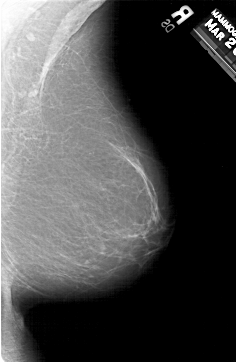

A_1308_1.RIGHT_CC

RIGHT_CC LINES 5986 PIXELS_PER_LINE 3391 BITS_PER_PIXEL 12 RESOLUTION 43.5 NON_OVERLAY